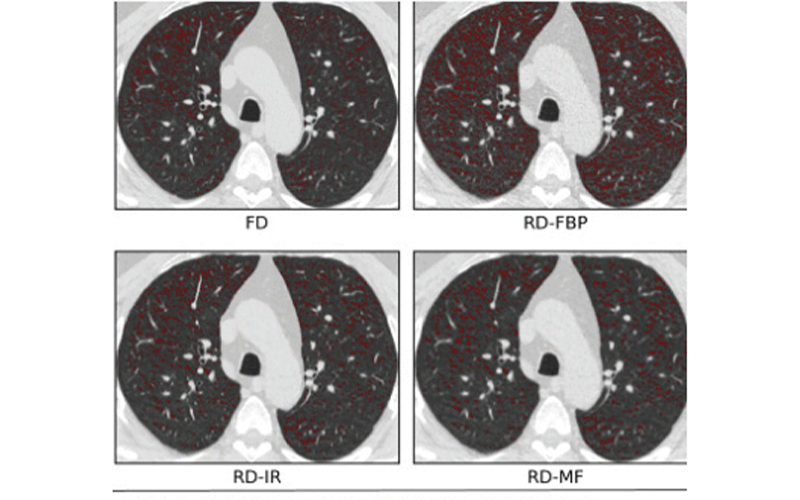

From pubs.rsna.org

Chest CT Findings in Marijuana Smokers Radiology Ct Scan Guidelines For Smokers  The initial assessment helps to.  there is evidence that screening people based on their risk of lung cancer can save lives.   patients will have their risk of cancer assessed based on their smoking history and other factors and those.   a low dose ct scan helps to check for changes in the lungs that may be lung cancer. Ct Scan Guidelines For Smokers.